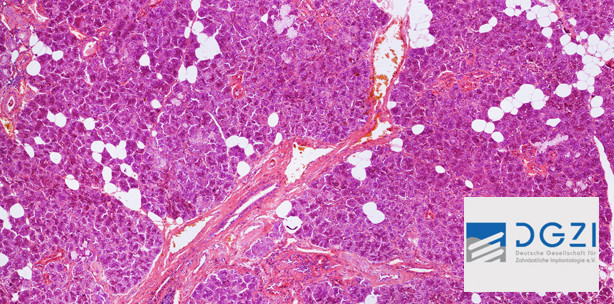

Die DGZI unterstützt aus ihrem Wissenschaftsfond eine wissenschaftliche Studie im Labor für Oralbiologische Grundlagenforschung an der Zahnklinik der Universität Bonn zur histologischen Untersuchung von Biopsien aus mit Knochenersatzmaterial (KEM) augmentierten Bereichen.